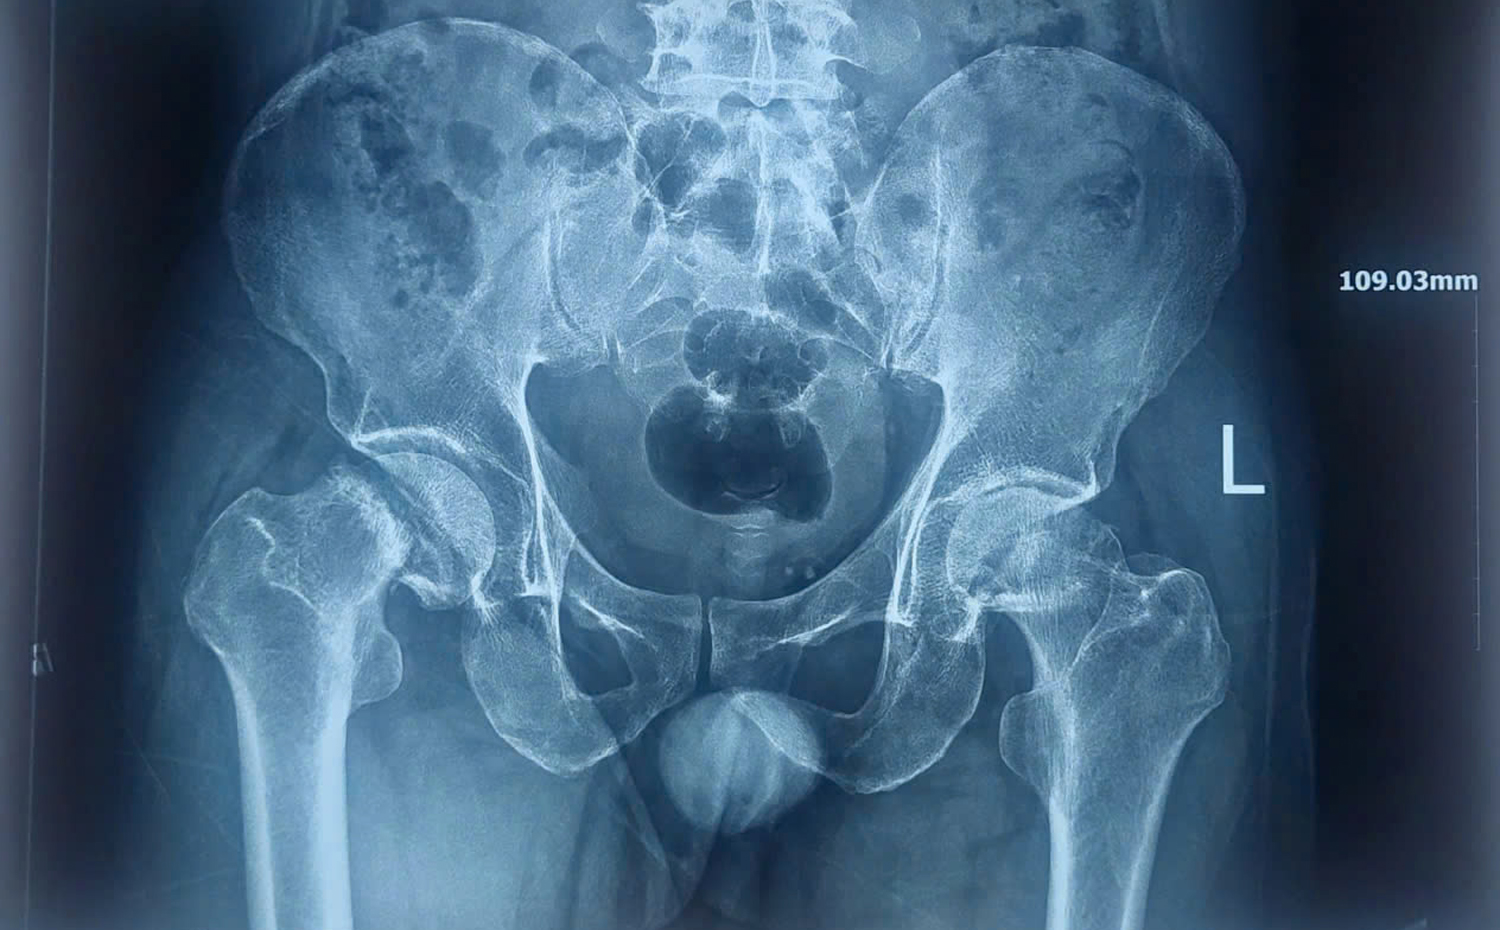

X-Quang khung chậu trước phẫu thuật.

Qua thăm khám và các xét nghiệm hình ảnh, bác sĩ xác định bệnh nhân bị hoại tử chỏm xương đùi hai bên – một bệnh lý nguy hiểm của khớp háng do giảm hoặc mất nguồn máu nuôi chỏm xương đùi, dẫn đến hoại tử xương. Bệnh lý này gây đau kéo dài và có thể xẹp khớp nếu không điều trị kịp thời nên bác sĩ chỉ định phẫu thuật.